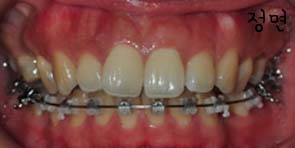

먼저 현재상태를 전반적으로 볼까요??

다음은 초기와 현재5월의 상태를 비교해보았어요 좀 변화가 보이나요~??